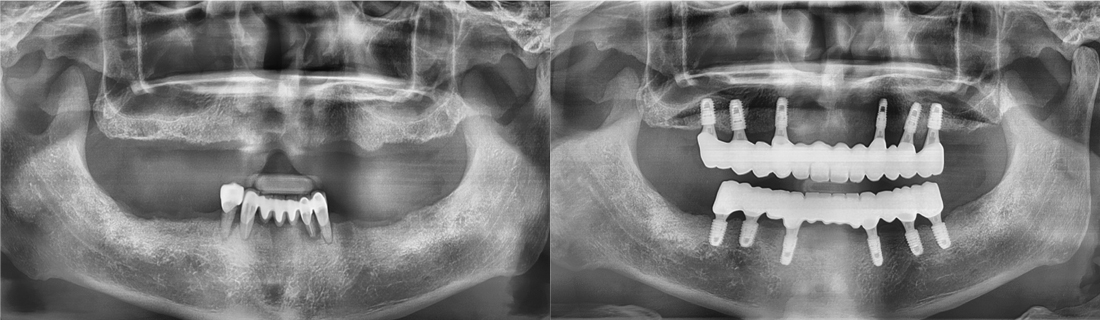

백년치과를 만나기 전과 후

나의 치아 사례와 비슷한 환자분들이 치료 후 어떻게 변화되었는지 직접 확인해보세요.

백년치과 임플란트를 만나기 전과 후